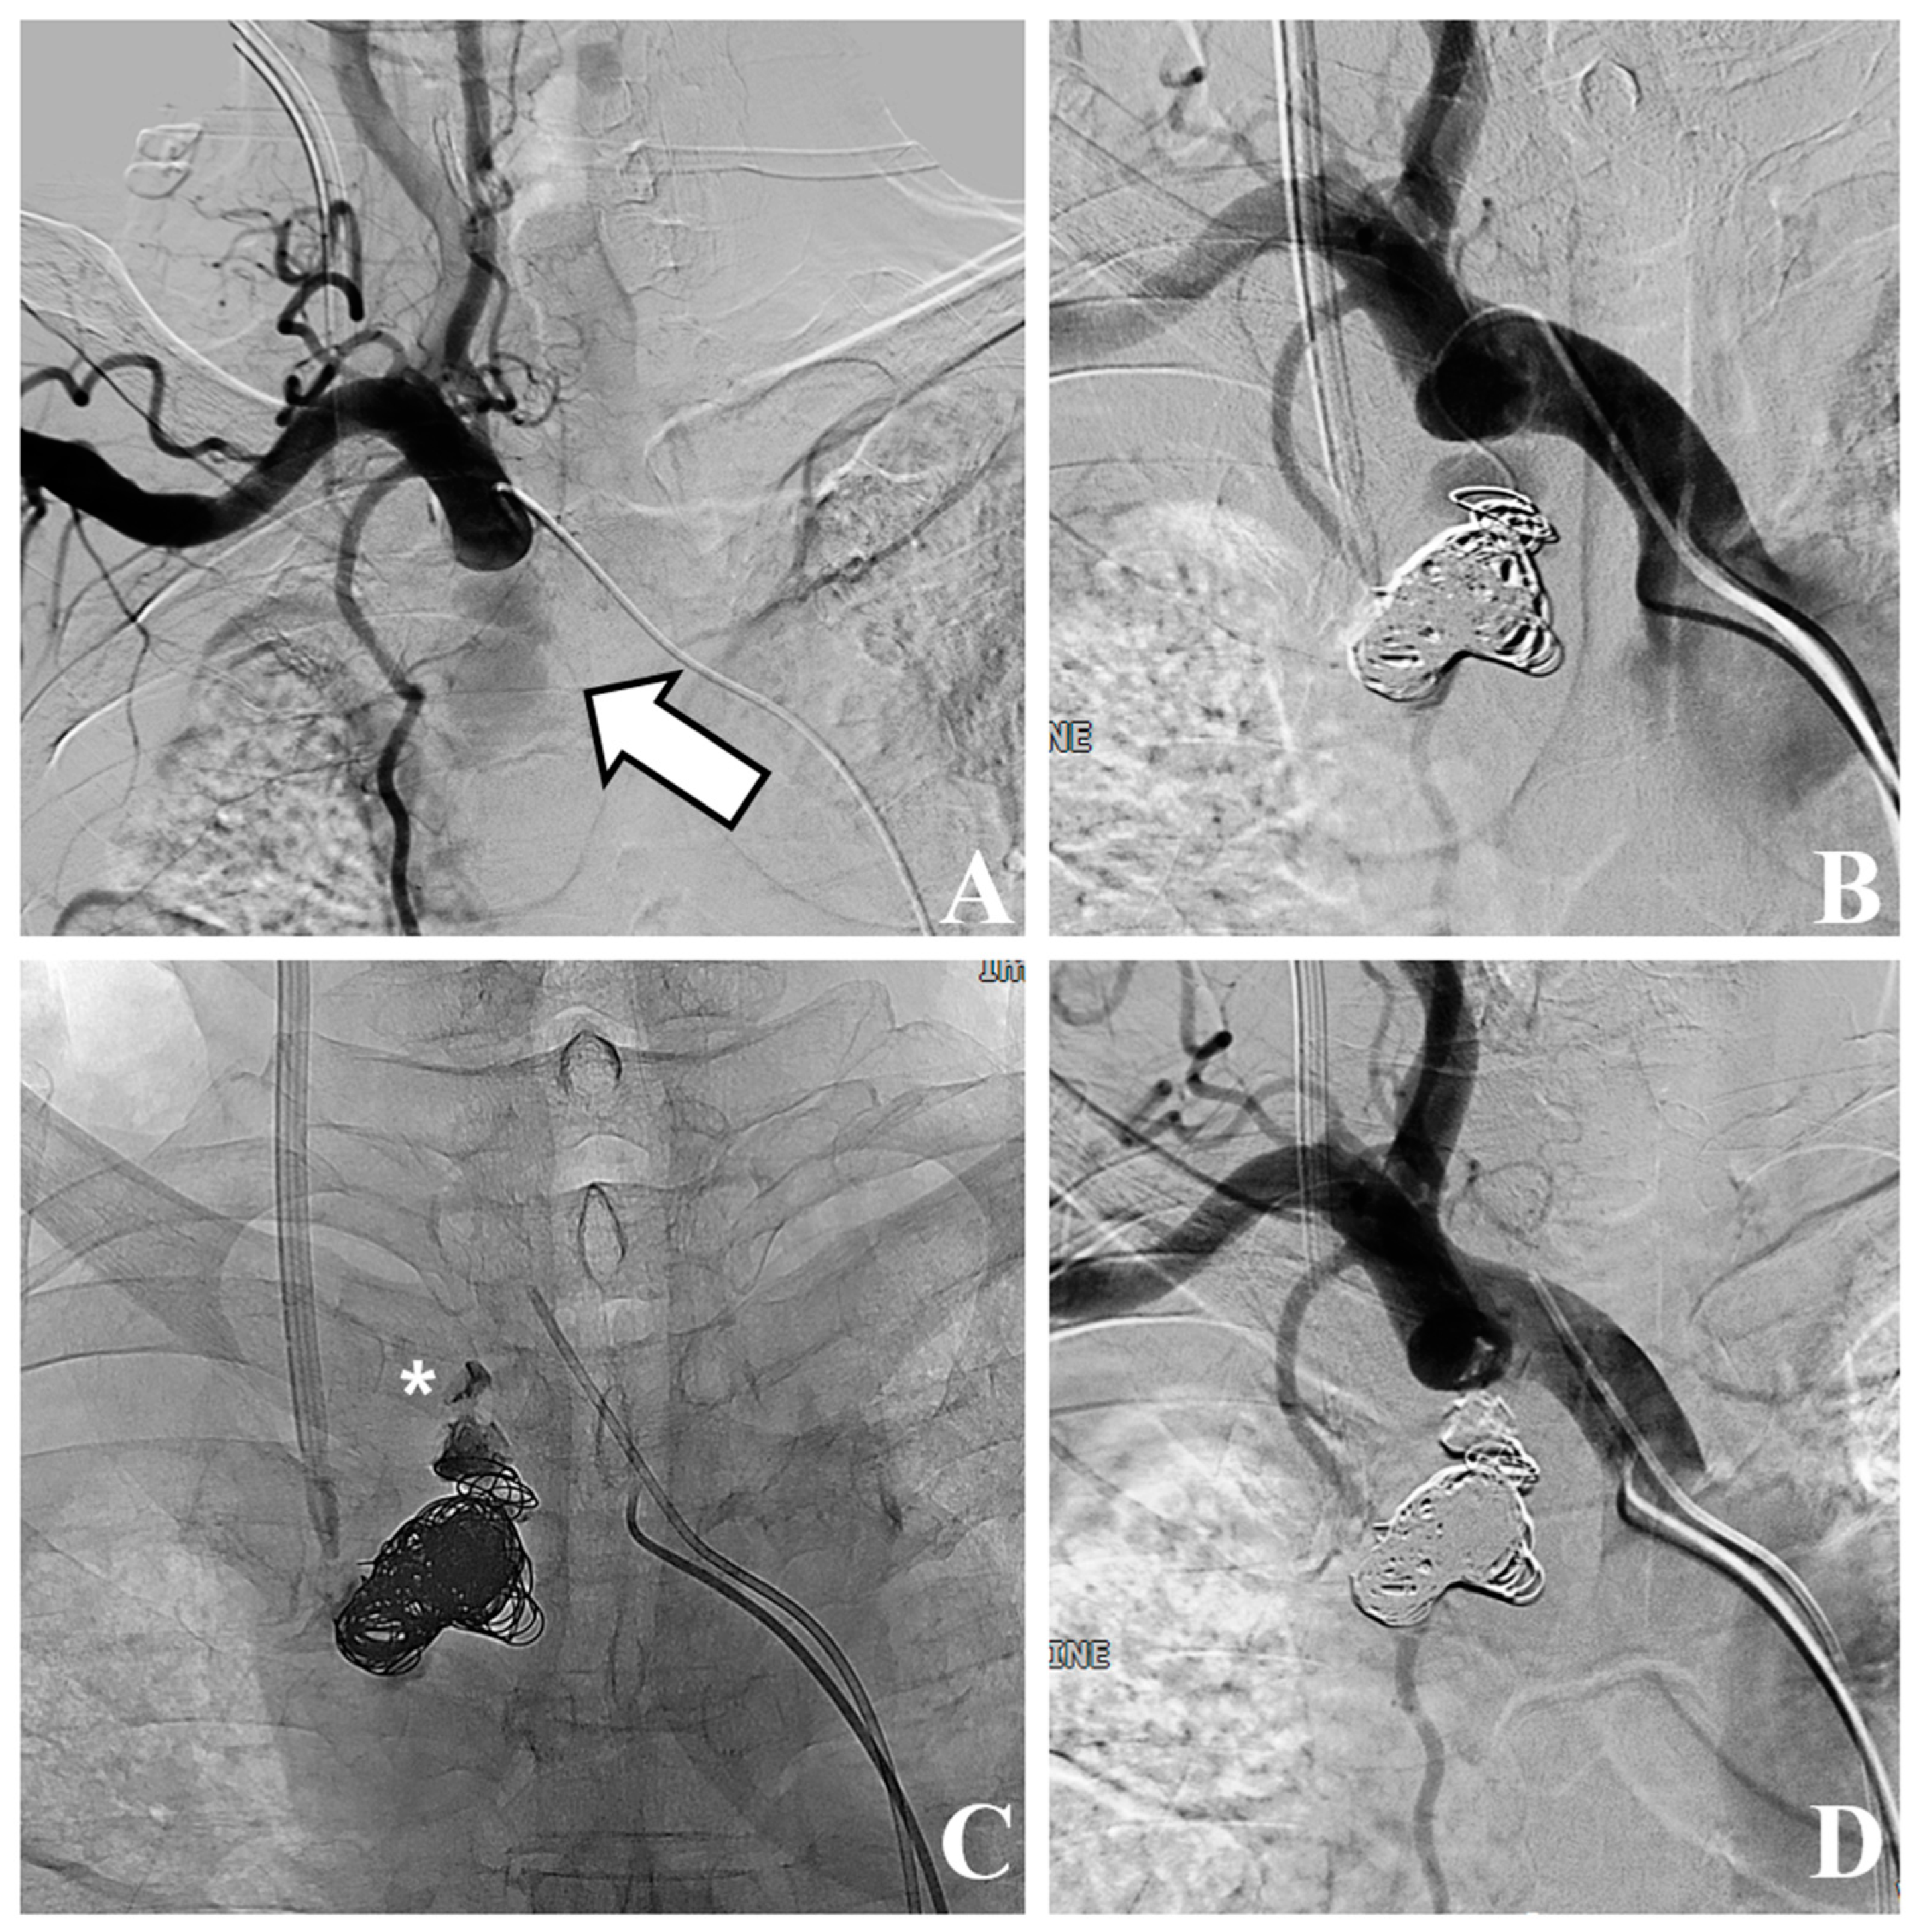

2. Case Presentation